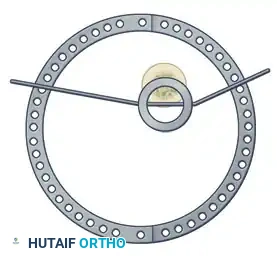

Step 3: Multi-Planar Fracture Reduction Using Olive Wires

Olive wires (wires with a small metal bead or "olive" forged into them) are powerful tools for translating bone fragments and achieving final reduction.

- Coronal Plane Correction: Use arched olive wires for final fracture reduction. For residual displacement in the coronal plane, place an olive wire in a transverse fashion (ensuring it passes through a safe anatomical zone).

- Apply tension to the wire without securing it tightly to the frame on the opposite side. The tensioner will pull the olive—and consequently the bone fragment—toward the tensioner, correcting the translation.

- Use continuous image intensification to ensure adequate reduction is achieved without over-translating the fragment.

- Once adequate correction is obtained in the coronal plane, secure the wire to the frame on the olive side.

- Sagittal Plane Correction: If further correction is required in the sagittal plane, connect another olive wire in an arched fashion. Tensioning this arched wire will impart a directional force vector to the bone, achieving final sagittal alignment.